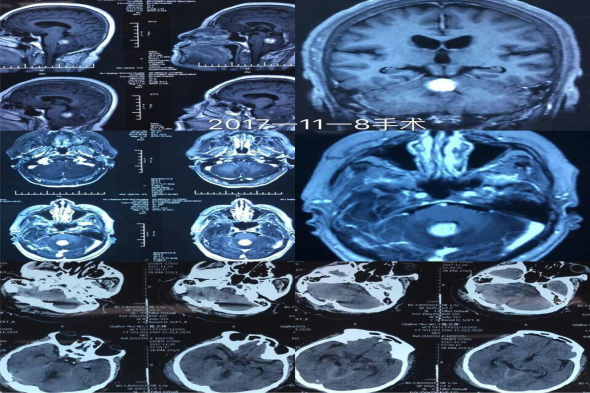

患者徐某,63岁,3周前老人突然出现站立不稳,走路向一侧偏斜,并有头晕不适等症状,家人立即带老人到当地医院就诊,以脑血管病对症治疗,但是症状不见好转。之后慕名来到我院入住神经外二科,经过一系列的CT、核磁检查,在脑干、小脑蚓部发现了一处占位性病变,脑桥粘连并明显受压,随时有生命危险。而且患者的肿瘤位于脑干、位置深,稍有不慎即可造成致死致残,手术风险极高。经过完善的术前准备后,11月8日,在科室主任吴卫东的带领下进行手术,无影灯下,生命禁区,手术刀在世界上最精密、最复杂的脑干神经网中精准游走,丝毫不差,采用后正中入路,在显微镜下有条不紊的分离、切开小脑蚓部,保护桥脑、仔细分离、逐块完全切除肿瘤,手术非常成功。术后患者意识清醒,无偏瘫失语、面瘫及共济失调等并发症,目前患者恢复良好。

术前、术后检查